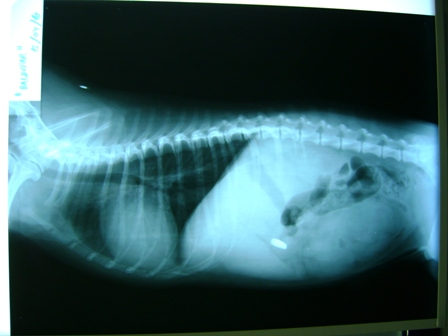

Si tu perro o tu gato tienen más de 8 años es el momento de realizar un plan geriátrico. Ayúdale a prevenir las posibilidades de padecer enfermedades a partir de los 8 años de edad como consecuencia del envejecimiento natural. Realiza un plan geriátrico mediante una serie de pruebas físicas y analíticas, mejorará la calidad de vida de tu mascota.

Revisaremos huesos y articulaciones, auscultaremos tórax y abdomen, realizaremos análisis de sangre, orina, parásitos, radiografías e incluso electrocardiograma. En nuestro plan geriátrico estudiaremos el estado general, nutricional, de la piel, ojos, oídos y cavidad bucal. Con ello, podremos evaluar el estado de salud de nuestras mascotas y asesorarle sobre su manejo a partir de esa edad, aplicando tratamientos específicos si son necesarios o aconsejando sencillos cuidados para disfrutar durante más tiempo de su compañía.